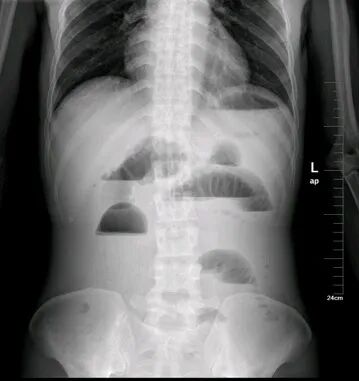

大肠癌

大肠癌是常见的恶性肿瘤,包括结肠癌和直肠癌。大肠癌的发病率从高到低依次为直肠、乙状结肠、盲肠、升结肠、降结肠及横结肠,近年有向近端(右半结肠)发展的趋势。其发病与生活方式、遗传、大肠腺瘤等关系密切。发病年龄趋老年化,男女之比为1.65:1。

升结肠癌并广泛转移

升结肠癌

升结肠癌并肝转移